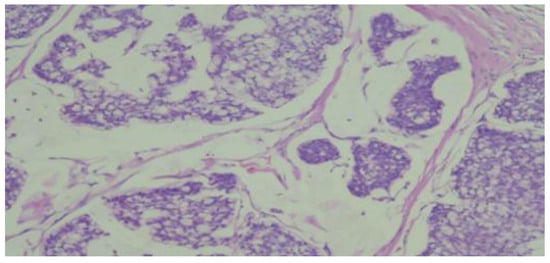

To establish a definitive diagnosis, a local anesthesia-guided core needle biopsy of the right breast was performed, obtaining 4 tissue fragments with a cumulative size of 25x1 mm. The microscopic histological structure suggested a Grade II SBR mucinous carcinoma (Figure 3).

Figure 3. Microphotography of the histopathological smear of the breast puncture biopsy shows abundant extracellular mucin and the cancer cells are scattered in the mucus basins.

The mucinous carcinoma component is composed of nests and cribriform-like structures floating in mucin lakes; tumor cells are polygonal, of medium size, with faint and focal cell boundaries, eosinophilic or pale cytoplasm, intracytoplasmic clear vacuoles, and small euchromatic nuclei, with some exhibiting a signet ring cell appearance (HE10X).